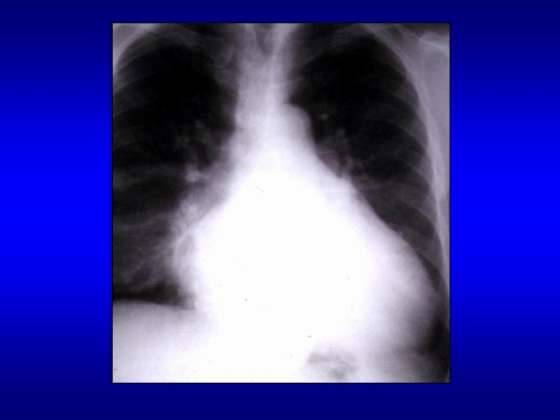

Radiografia cardiopulmonara

Semnele

radiologice sunt diferite in raport cu forma de insuficienta

mitrala acuta sau cronica

In insuficienta

mitrala acuta se constata:

- atriul stang normal sau mic;

- staza pulmonara (hil stufos, linii

Kerley)

mitrala cronica se constata:

- atriul stang enorm enorm;

- ventricul stang marit, ulterior

ventricul drept marit datorita supraincarcarii

sistolice;

- indice cardiotoracic marit peste 0,5;

- calcificari de inel mitral;

- hiluri si circulatie

pulmonara incarcate ( HTP venoasa, linii Kerley);

- dilatarea arterei pulmonare.